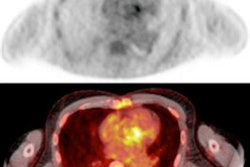

Infective endocarditis is a very serious disease that is notoriously tricky to diagnose. Echocardiography is operator-dependent, and its sensitivity can decrease in patients with valvular prostheses, so molecular imaging's role is growing rapidly in this area.

The results of three important PET/CT studies from Portugal, France, and Italy were unveiled at the recent European Society of Cardiology virtual congress. They shine a light on infective endocarditis. Don't miss our exclusive report.